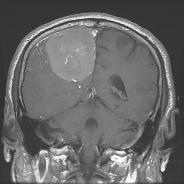

수막종은 축외 뇌종양 중 가장 발생빈도가 높은 종양으로 원발 뇌종양의 약 25%를 차지합니다. 주로 40~50대 성인에 많이 발생하고 2:1의 비율로 여자에게서 더 많이 발생한다고 알려져 있습니다. 수막종은 수술만으로 완치될 가능성이 매우 높은 양성종양으로, 뇌를 지지하는 뇌막인 수막(meninges)의 구성 성분인 지주막세포에서 기원한다고 알려져 있습니다. 수막종은 지주막 세포가 분포한 곳에서는 어디서나 발생하지만, 이들 세포의 밀도가 높은 시상 정맥동 주변, 대뇌궁륭부, 뇌바닥, 후두개와 등에서 더 빈번하게 발생합니다.

수막종은 성장 방식 및 종양의 성상에 몇 가지 특징을 가집니다. 이 종양은 대부분 뇌경막에서 발생하여 딱딱한 두개골 때문에 밖으로 자라지 못하고 거의 항상 뇌조직 쪽으로 자랍니다. 그러나 침습적인 성장이 아니어서 뇌조직과 종양 사이에 연뇌막은 물론 뇌척수액을 포함한 지주막이 대부분 잘 보존되며, 이로 인해 신경학적 장애를 초래하지 않고 종양을 절제할 수 있습니다. 종양 자체는 단단하고 혈관분포가 풍부한 것이 특징입니다.